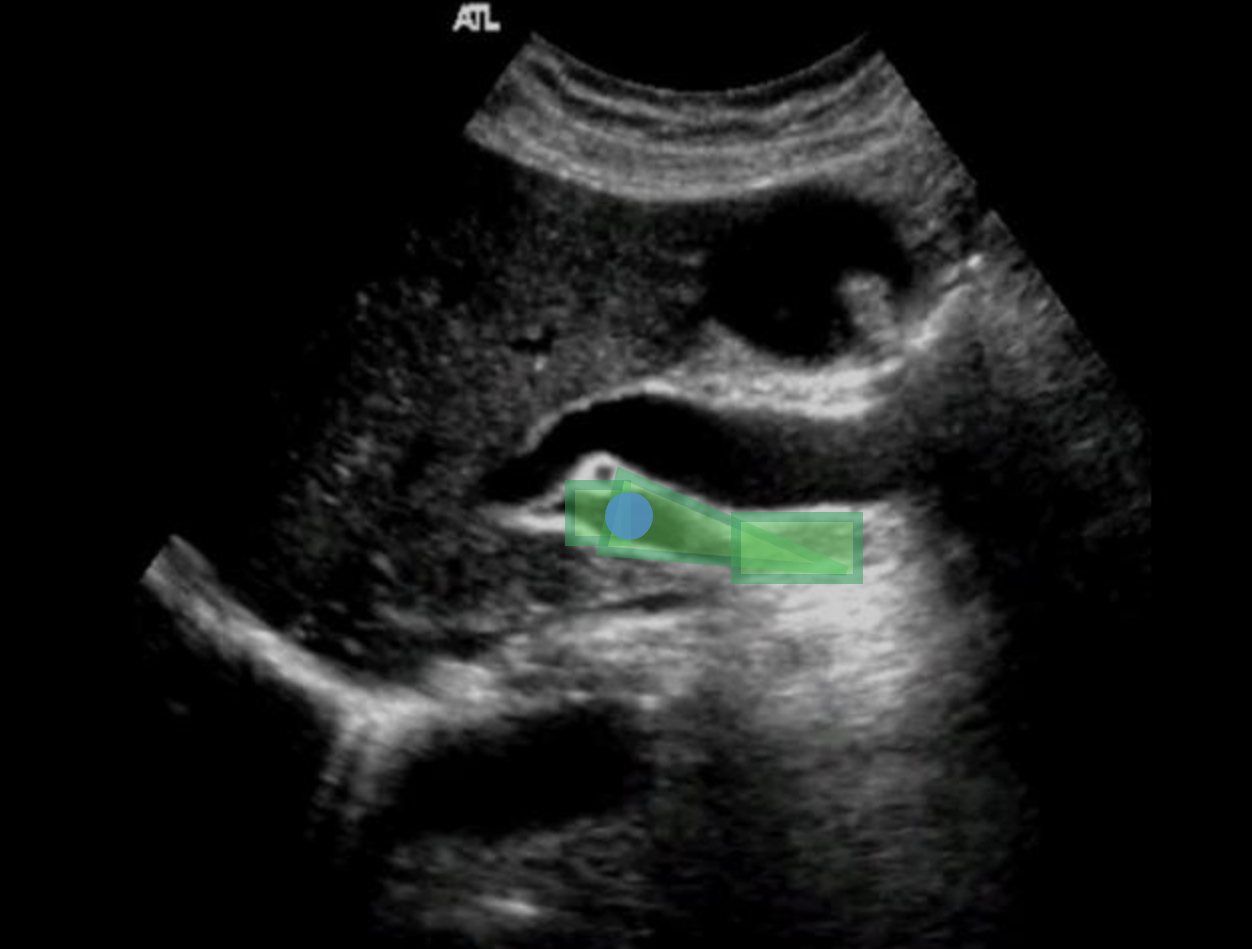

Which waveform represents a normal portal vein waveform? Use your mouse to position your cursor over the correct waveform and click to set the answer.

***the color map displayed applies to all displayed Doppler tracings.

What structure is indicated by the blue arrow?

right portal vein |

What structure is indicated by the green arrow?

Main portal vein |

What structure/vessel is indicated by #2?

left portal vein